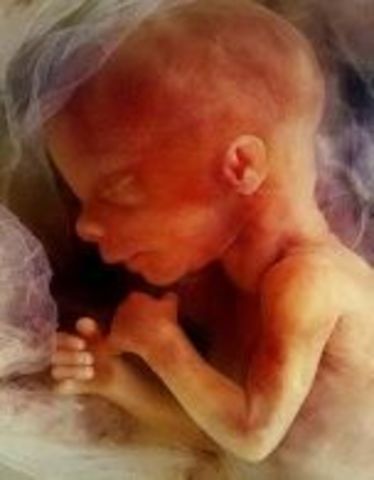

Week 27

third Trimester begins. Fetus is now able to open eyes however still not able to see.

• Week 28

Week 28

Hair is visible through 4D ultrasounds. Milk teeth have started growing under the gums and eyes start to move.